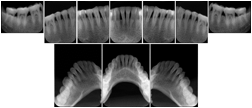

OO.1.2 Ophthalmology

1. A patient in rural Canada visits a general ophthalmologist and is found to have diabetic macular edema. The general ophthalmologist would like to discuss the case with a retina specialist before performing laser surgery. A fluorescein angiogram is done with multiple retinal images taken in a timed series after an intravenous injection. The images along with a Structured Display are shared via a Health Information Exchange with a retina specialist in Calgary, who opens them using his Ophthalmology EMR software and consults via phone with the general ophthalmologist. Both physicians view the images in the same layout so the retina specialist can provide accurate guidance for treating the patient.

2. A patient in rural Iowa visits his primary care physician for management of diabetes. Three non-mydriatic (patient's eyes are not dilated) photographs are taken of the back of each eye, and forwarded electronically along with a Structured Display to an ophthalmologist in Iowa City. The ophthalmologist reads the photos in an agreed upon layout so there is no mistake about what portion of which eye is being viewed. The ophthalmologist is able to tell the primary care physician that his patient does not need to come to Iowa City for face to face ophthalmologic care, but that there is a particular view of the left eye that should be photographed again in 6 months.

Ophthalmic Retinal Study Structured Display

Figure OO-3. Ophthalmic Retinal Study Structured Display

3. A patient in rural Minnesota experiences sudden vision loss and goes to a general ophthalmologist, who acquires OCT images and forwards them electronically along with a Structured Display to a retina specialist six travel hours away. The retina specialist is able to view the images in the standard layout that he is comfortable with, and to confirm that the patient has a choroidal neovascular membrane. He determines that is would be worthwhile for the patient to travel for treatment.

OCT Retinal Study with Cross Section and Navigation Structured Display

Figure OO-4. OCT Retinal Study with Cross Section and Navigation Structured Display